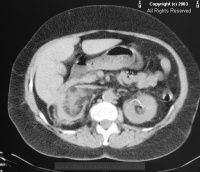

静脉肾盂造影示肾盂、肾盏变形、缩窄,双肾形态学检查(B超、CT等)显示肾影不规则,甚至缩小;肾小管功能有持续性损害,如尿渗透压降低,尿视黄醇结合蛋白及尿β2微球蛋白升高。

X线检查:腹部平片可见一侧或双侧肾脏缩小,且不规则。有时可见尿路结石。尿路造影可发现慢性肾盂肾炎的特征性表现,如肾盂扩张,以及其表面肾实质瘢痕形成或萎缩,肾实质变形,造影剂显影不良和显影延迟。

在单侧萎缩性肾盂肾炎,其对侧肾脏代偿性扩大。如有膀胱输尿管返流,则出现输尿管扩张。逆行尿路造影亦可见相似的表现,逆行膀胱尿道造影可发现膀胱输尿管返流,尤其是儿童患者更为常见。